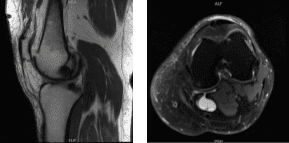

The patient brought an MRI results, for her left knee, denudation of articular cartilage in the anterior compartment of the knee and tricomparmental marginal bony spurring. Intrasubstance degeneration in the posterior horn of the medial meniscus.

No definite surfacing medial or lateral meniscal tear is seen. Moderate sized Baker’s cyst. For the right knee, Complex degenerative tear in the medial meniscus extending from the body into the posterior horn into the posterior root with extrusion. Tricomparmental articular cartilage denudation with marginal bony spurring.

MRI-3T Left knee non-contrast